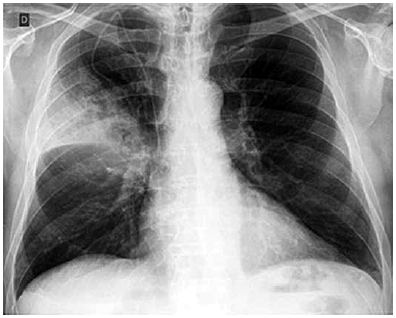

Paciente masculino de 69 anos dá entrada no pronto -socorro com queixa de tosse e expectoração amarelada há 4 dias. Relata febre alta não aferida, calafrios e sudorese noturna. Relata dois episódios de fezes líquidas no período. Nega cefaleia, disúria ou lesões de pele. Refere diabetes mellitus e hipertensão arterial sistêmica com tratamento irregular. Tabagista com carga tabágica de 30 maços/ano.

Ao exame, encontra-se em REG, consciente e orientado, desidratado ++/4+; temperatura axilar 38 oC; FR 22 irpm, PA 120 x 70, ritmo cardíaco regular em 2 tempos sem sopros; FC 124 bpm, MV presente com EC em base e 1/3 médio HTD, saturação O2 92% em ar ambiente, dextro 340 mg/dL.

RX de tórax: